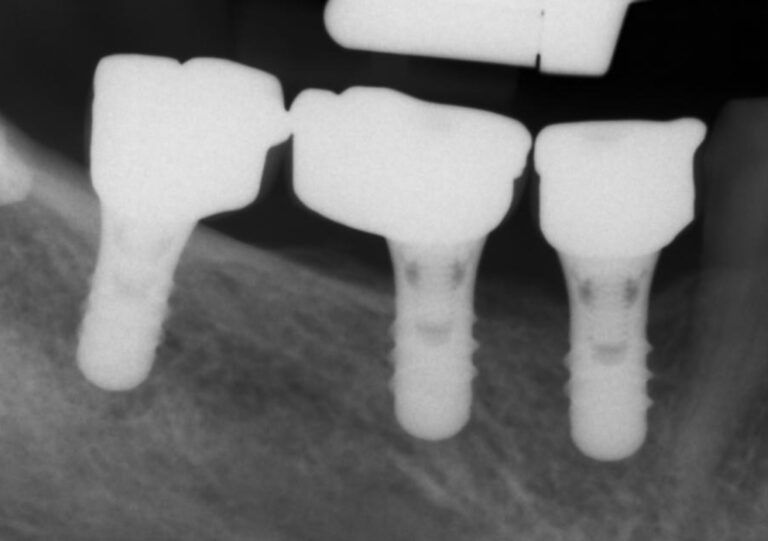

In conclusion, I still maintain the view that a Bone Level implant is a versatile and effective platform, which allows more freedom for individualisation than the Tissue level. That is of course in the hands of a well-trained clinician, who understand the basic design principles of the Implant Supracrestal Complex. On the other hand, if in the hands of an ill trained clinician, a Tissue Level will act as the safety break: it will prevent the worse of the design mistakes. That might be a significant advantage in large scale, which however would go unnoticed in the studies, as most of them are conducted at University clinics by experts who are well aware of design principles and maintenance. At the same time, having been a recipient centre for all sorts of complications in the last decade, I have seen many impossible prosthetic designs on Tissue Level implants, which would probably never make it far if they were on Bone Level implants.

Prosthetic designs such as the implants above would go against anything we know about proper emergence profile. On bone level implants, such a prosthesis would have caused massive marginal bone loss. The collar however, forcing 2.8 mm of height under 13o appears to have saved the day.